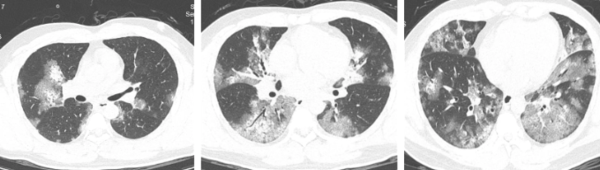

Kết quả cho thấy anh Lưu dương tính với cúm A. Điều đáng lo ngại hơn là hình ảnh CT cho thấy cả hai lá phổi của anh đều bị tổn thương nghiêm trọng, xuất hiện tình trạng mờ kính, hay còn gọi là "phổi trắng". Bác sĩ Lữ Quần, khoa Hô hấp và Hồi sức cấp cứu, Bệnh viện trực thuộc Đại học Sư phạm Hàng Châu, cho biết tình trạng "phổi trắng" thường gặp ở các trường hợp viêm phổi do virus như cúm gia cầm độc lực cao hoặc Covid-19. Tuy nhiên, trường hợp diễn biến nặng từ cúm A thông thường sang "phổi trắng" như anh Lưu khá hiếm gặp. Nồng độ oxy trong máu của anh Lưu đã giảm xuống 85%. May mắn thay, nhờ sự nỗ lực của đội ngũ y tế, tình trạng của anh dần ổn định.

Kết quả chụp CT của ông Lưu cho thấy tình trạng phổi trắng. (Ảnh/Trích từ Qianjiang Evening News)